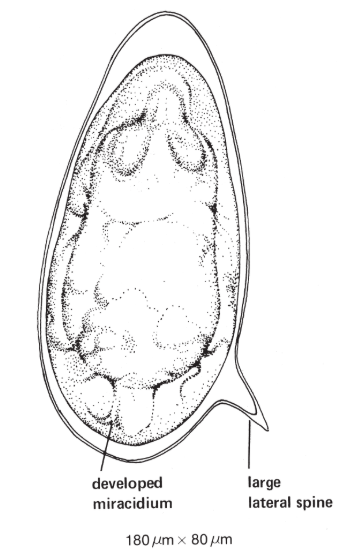

23

New cards

Schistosoma mansoni (Manson’s blood fluke)

knowt flashcard image